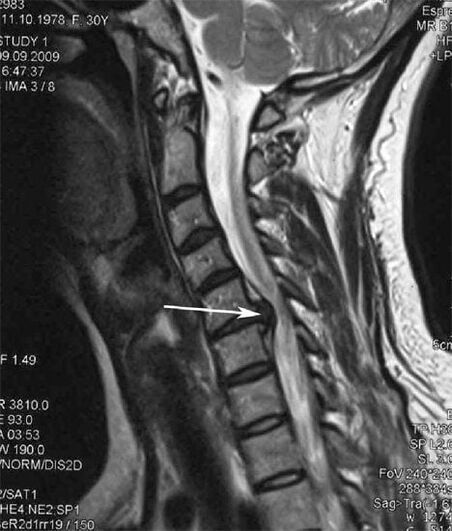

In the initial stages, osteochondrosis is detected using MRI..Subsequently, the pathology can be diagnosed by x-ray.On x-rays of the cervical spine, a decrease in the distance between the vertebrae, pathological changes in the facet joints and osteophytosis are noted.

Many people complain that they cannot turn their neck due to severe pain that occurs after suddenly lifting something heavy.This phenomenon indicates the formation of a herniated disc.The cause of pain in the back, neck and upper extremities is the pinching of one of the nerve roots emerging from the spinal cord.